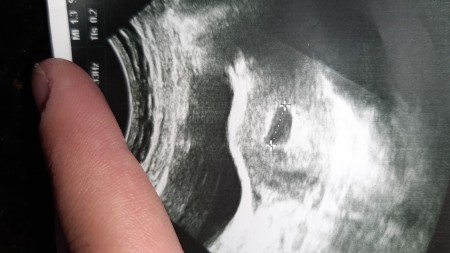

Sizce burda bebek varmı nokta bişey var ama o bebekli bilemedim ilk gebeliğin o yüzden pek anlayamadım yardımcı olurmusunuz ?

Gebelik haftası 6+5

Dr unuz demedimi bebek var yok diye.Demedi ise sorsaydiniz  keske.Bu haftalarda nokta gibi gozukuyorda onu ancak dr gorur bilir.

2 hafta sonra gel dedi gönderdi bende bi nokta gibi bişey gördüm sanki merak ettim o yüzden

O siyahlık kese ilk kese oluşur sonra içinde bebek olur inşallah. Dikkat et 2 hafta sonra hem bebeği hem kalp atışını duyarsın inşallah.

6. Haftada bendede oyle nokta vardi bebek olusmaya basliyor 8. Haftada tam gormustm bebegi